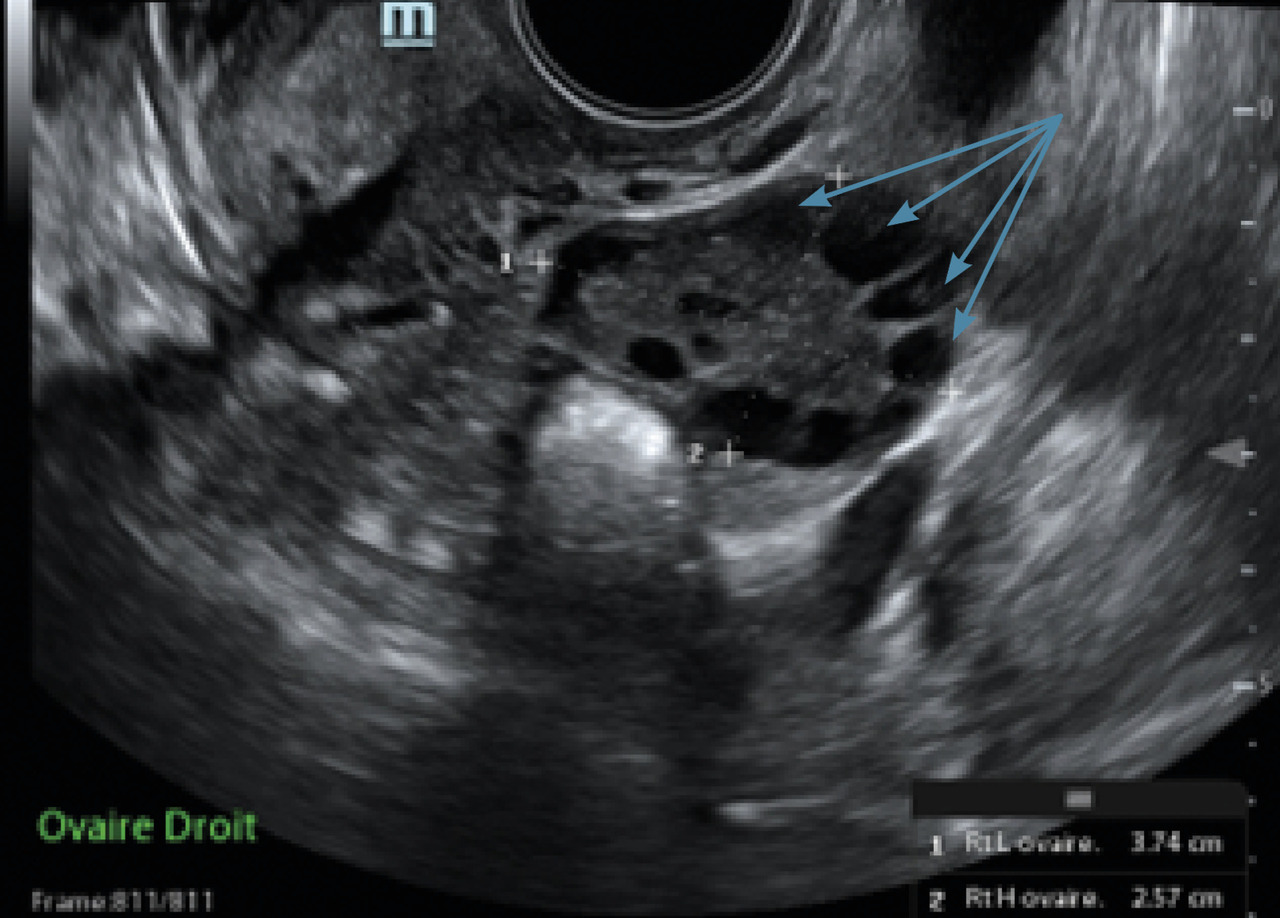

L’immense majorité des cas d’aménorrhée secondaire est due à un SOPK (fig. 3 et 4).

Le SOPK concerne 10 à 15 % des femmes.3 Le surpoids ou l’obésité sont fréquents mais ne sont pas nécessaires au diagnostic.

Ce syndrome est défini par la présence d’au moins deux des trois critères suivants :

• une oligo- ou anovulation ;

• des signes d’hyperandrogénie clinique et/ou biologique ;

• un compte des follicules antraux (CFA) supérieur ou égal à 20 par ovaire (ou un volume ovarien augmenté, supérieur à 10 mL).

Le CFA correspond au compte des follicules antraux mesurant 2 à 9 mm à l’échographie par voie vaginale. Le dosage de l’AMH peut être utile car il est corrélé au nombre de follicules antraux.

Il n’est pas recommandé de réaliser une échographie pelvienne avec CFA pour le diagnostic de syndrome des ovaires polykystiques moins de huit années suivant la ménarche, en raison de la fréquence très élevée d’un aspect multifolliculaire des ovaires chez les adolescentes.